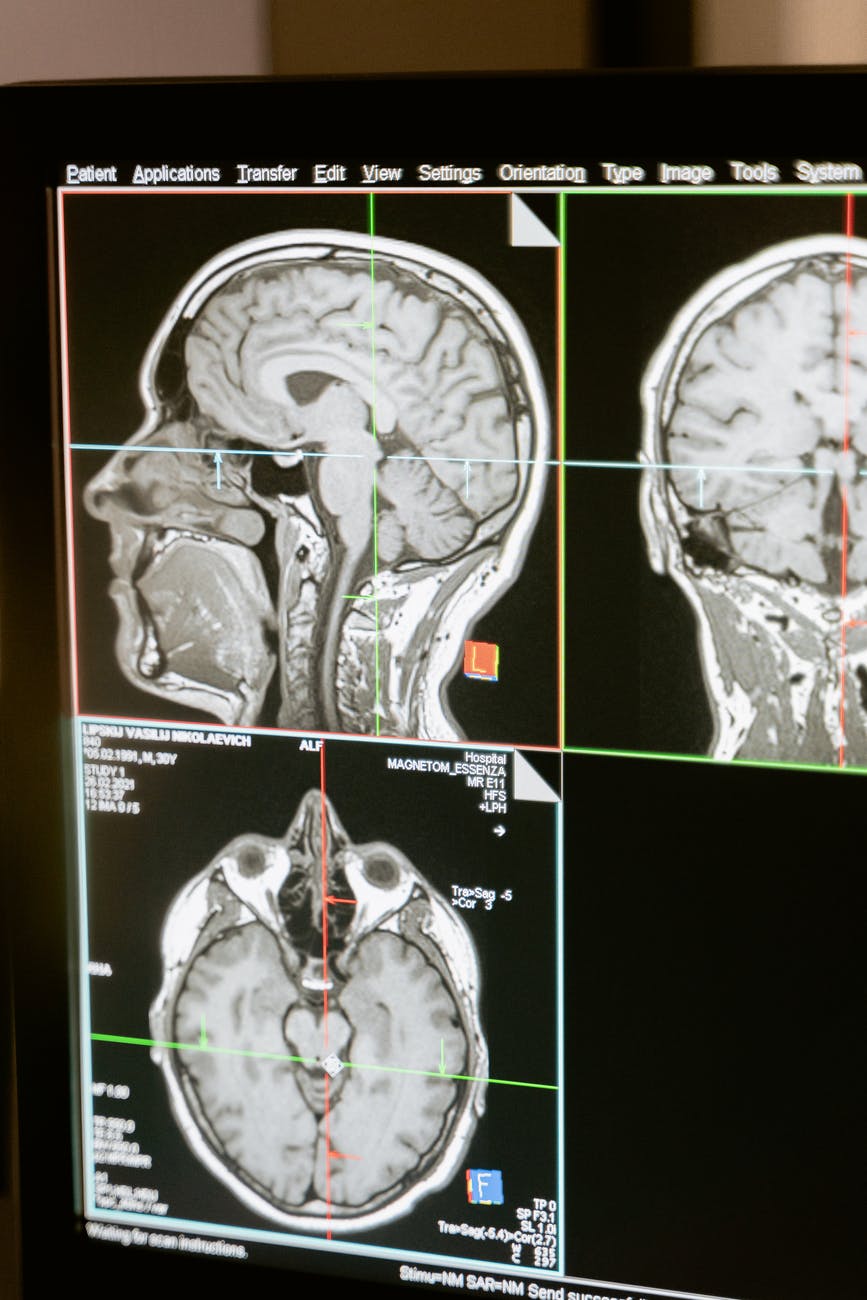

Cercetările sugerează că Neurofeedback-ul funcționează prin creșterea densității fusului orar de somn și stabilizarea părții sistemului nervos care reglează starea de veghe, somnul și excitarea. Un studiu care a comparat neurofeedback-ul cu intervențiile de biofeedback pentru o populație cu insomnie a constatat că tratamentul cu neurofeedback a dus la creșterea timpului total de somn, creșterea somnului REM și la scăderea perioadelor de trezire după apariția somnului. Cercetări recente confirmă participarea directă a frecvențelor Infraslow la menținerea etapelor de somn. Nu numai că frecvențele Infraslow au fost corelate cu stadiile de somn, ele au fost, de asemenea, corelate în studiile la om și animale cu fragilitatea menținerii somnului.

Clienții raportează în mod regulat că, după câteva sesiuni de Neurofeedback, sunt mai capabili să adoarmă, să rămână adormiți și să se odihnească timp de 7-8 ore necesare pentru o sănătate optimă. Neurofeedback-ul este deosebit de util în reglarea tulburărilor de somn. ISF îmbunătățește somnul învățând corpul să se relaxeze. Reduce anxietatea și mută sistemul nervos central în echilibru. Frecvențele infraslow au un impact direct asupra neuronilor din creier care influențează ritmurile noastre circadiene, ceasul nostru biologic de 24 de ore. Neurofeedback-ul oferă o alternativă la paradigma medicamentelor sedative, hipnotice, anticonvulsivante și unele antidepresive. Mai exact, Neurofeedback-ul reglează arhitectura somnului, astfel încât clienții noștri să poată dormi mai bine, în mod regulat. Îmbunătățirile aduse somnului au efecte profunde asupra calității vieții noastre.